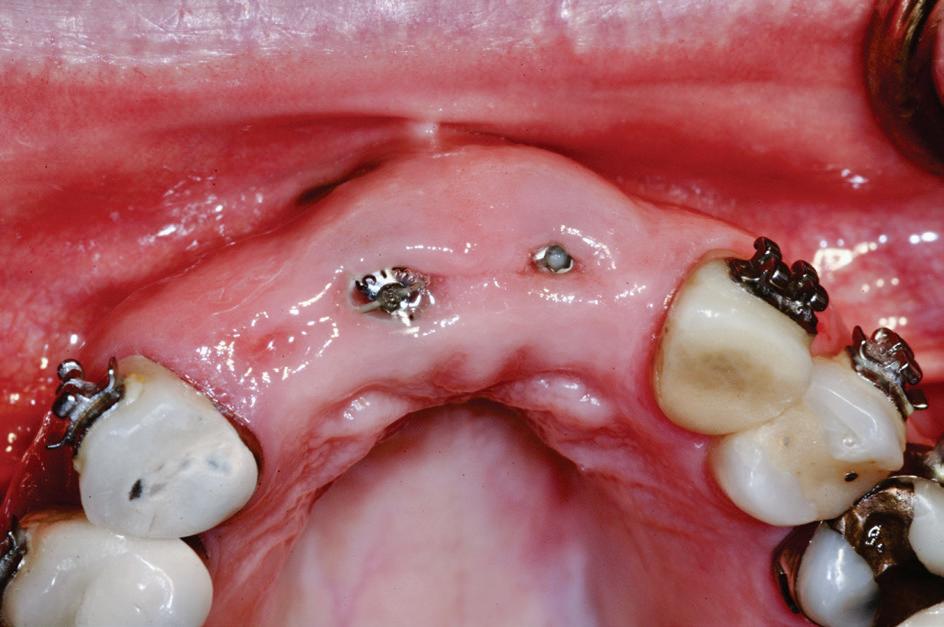

Pentru a obține mai multe informații, adesea este indicat un studiu volumetric prin tomografia computerizată cu fascicul conic (CBCT). Această imagistică avansată poate fi utilizată pentru evaluarea resorbției radiculare la dinții adiacenți, posibila transpoziționare între incisivul lateral maxilar și canin sau caninii maxilari care erup chiar deasupra apexului incisivilor laterali, dilacerațiile radiculare și anchiloza. În ceea ce privește resorbția radiculară, Ericson & Kurol au raportat că, pe baza CBCT, 38% dintre incisivii laterali, respectiv 9% dintre centralii maxilari au prezentat resorbție radiculară importantă în raport cu caninii impactați (fig. 2, 3).

2, 3. Scanările CBCT ale caninilor impactați palatinal; aspectul frontal (fig. 2) și ocluzal (fig. 3) 2 3